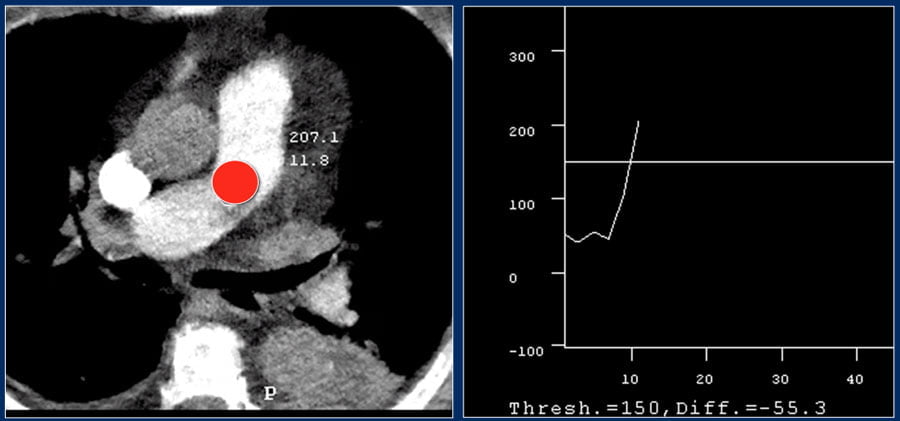

For good timing bolus tracking is needed.

A ROI is placed in the pulmonary trunk.

When the treshhold of 150 HU is reached, the patient is asked to breath in and scanning is started immediately.

Để chọn đúng thời điểm chụp, cần có bộ phận theo dõi nồng độ thuốc (bolus tracking).

Đặt con trỏ (ROI) vào vị trí thân động mạch phổi.

Khi nồng độ thuốc đạt tới 150 HU, nói bệnh nhân hít vào và nín thở, chụp ngay sau đó.